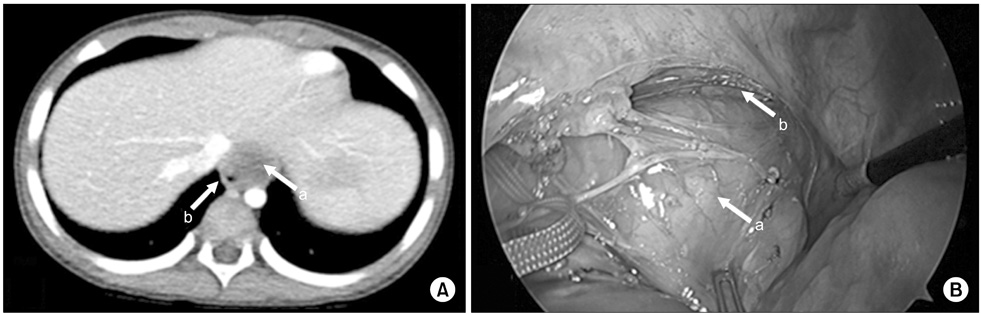

Esophageal duplication cyst located at posterior mediastinum. (A) The mass was abutting with anterior wall of esophagus on chest CT (2.5×1.9×2.5-cm-sized mass). (B) Mass was connected to muscle layer of esophagus. Arrows: a, mass; b, esophagus.

jkaps-23-29-g003.jpg

Fig. 3 Esophageal duplication cyst located at posterior mediastinum. (A) The mass was abutting with anterior wall of esophagus on chest CT (2.5×1.9×2.5-cm-sized mass). (B) Mass was connected to muscle layer of esophagus. Arrows: a, mass; b, esophagus.